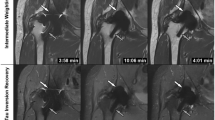

We found that following the attenuation and width of metal artifacts gradually decreased with increasing VMI settings, while the periprosthetic vascular attenuation worsened to below 200 HU. Similarly, the score of artifacts gradually improved as the increased keV level, while the score of overall vascular contour and diagnostic evaluation gradually increased at 50 – 80 keV and then decreased at 90–120 keV. This may be due to the impact of the artifact on the vessel being more obvious at low energy levels. Thus, we considered that 80 keV might be an acceptable energy level and equilibrium point to better visualize the periprosthetic artery and reduce metal artifacts (Fig. 4). In this level, the score of overall vascular contour and diagnostic evaluation increased to the top, and the score of artifacts showed most artifacts were removed (Fig. 5). Besides, the vascular attenuation was still over 200 HU and got a satisfied diagnostic confidence. In a study about stent evaluation in lower extremity DE-CTA, Mangold et al. reported 80 keV-VMI + improved image quality, stent visualization, and diagnostic confidence for stent evaluation [37]. In another study about peripheral artery stents, Zhang et al. demonstrated the optimal keV level for peripheral artery stents was concluded at 90 keV [38].

A series of axial enhanced CT images of a patient with THA. Images were reconstructed as CI, CIMAR, and VMIMAR at 50–120 keV with 10 intervals (window center 60 HU; window width 360 HU). Images show the metal artifact is gradually reducing with increasing energy level; however, the vascular visualization is worsening. The vascular visualization is terrible above 100 keV, while the vessel is disturbed by artifacts below 70 keV. The best performance is found at 80 keV